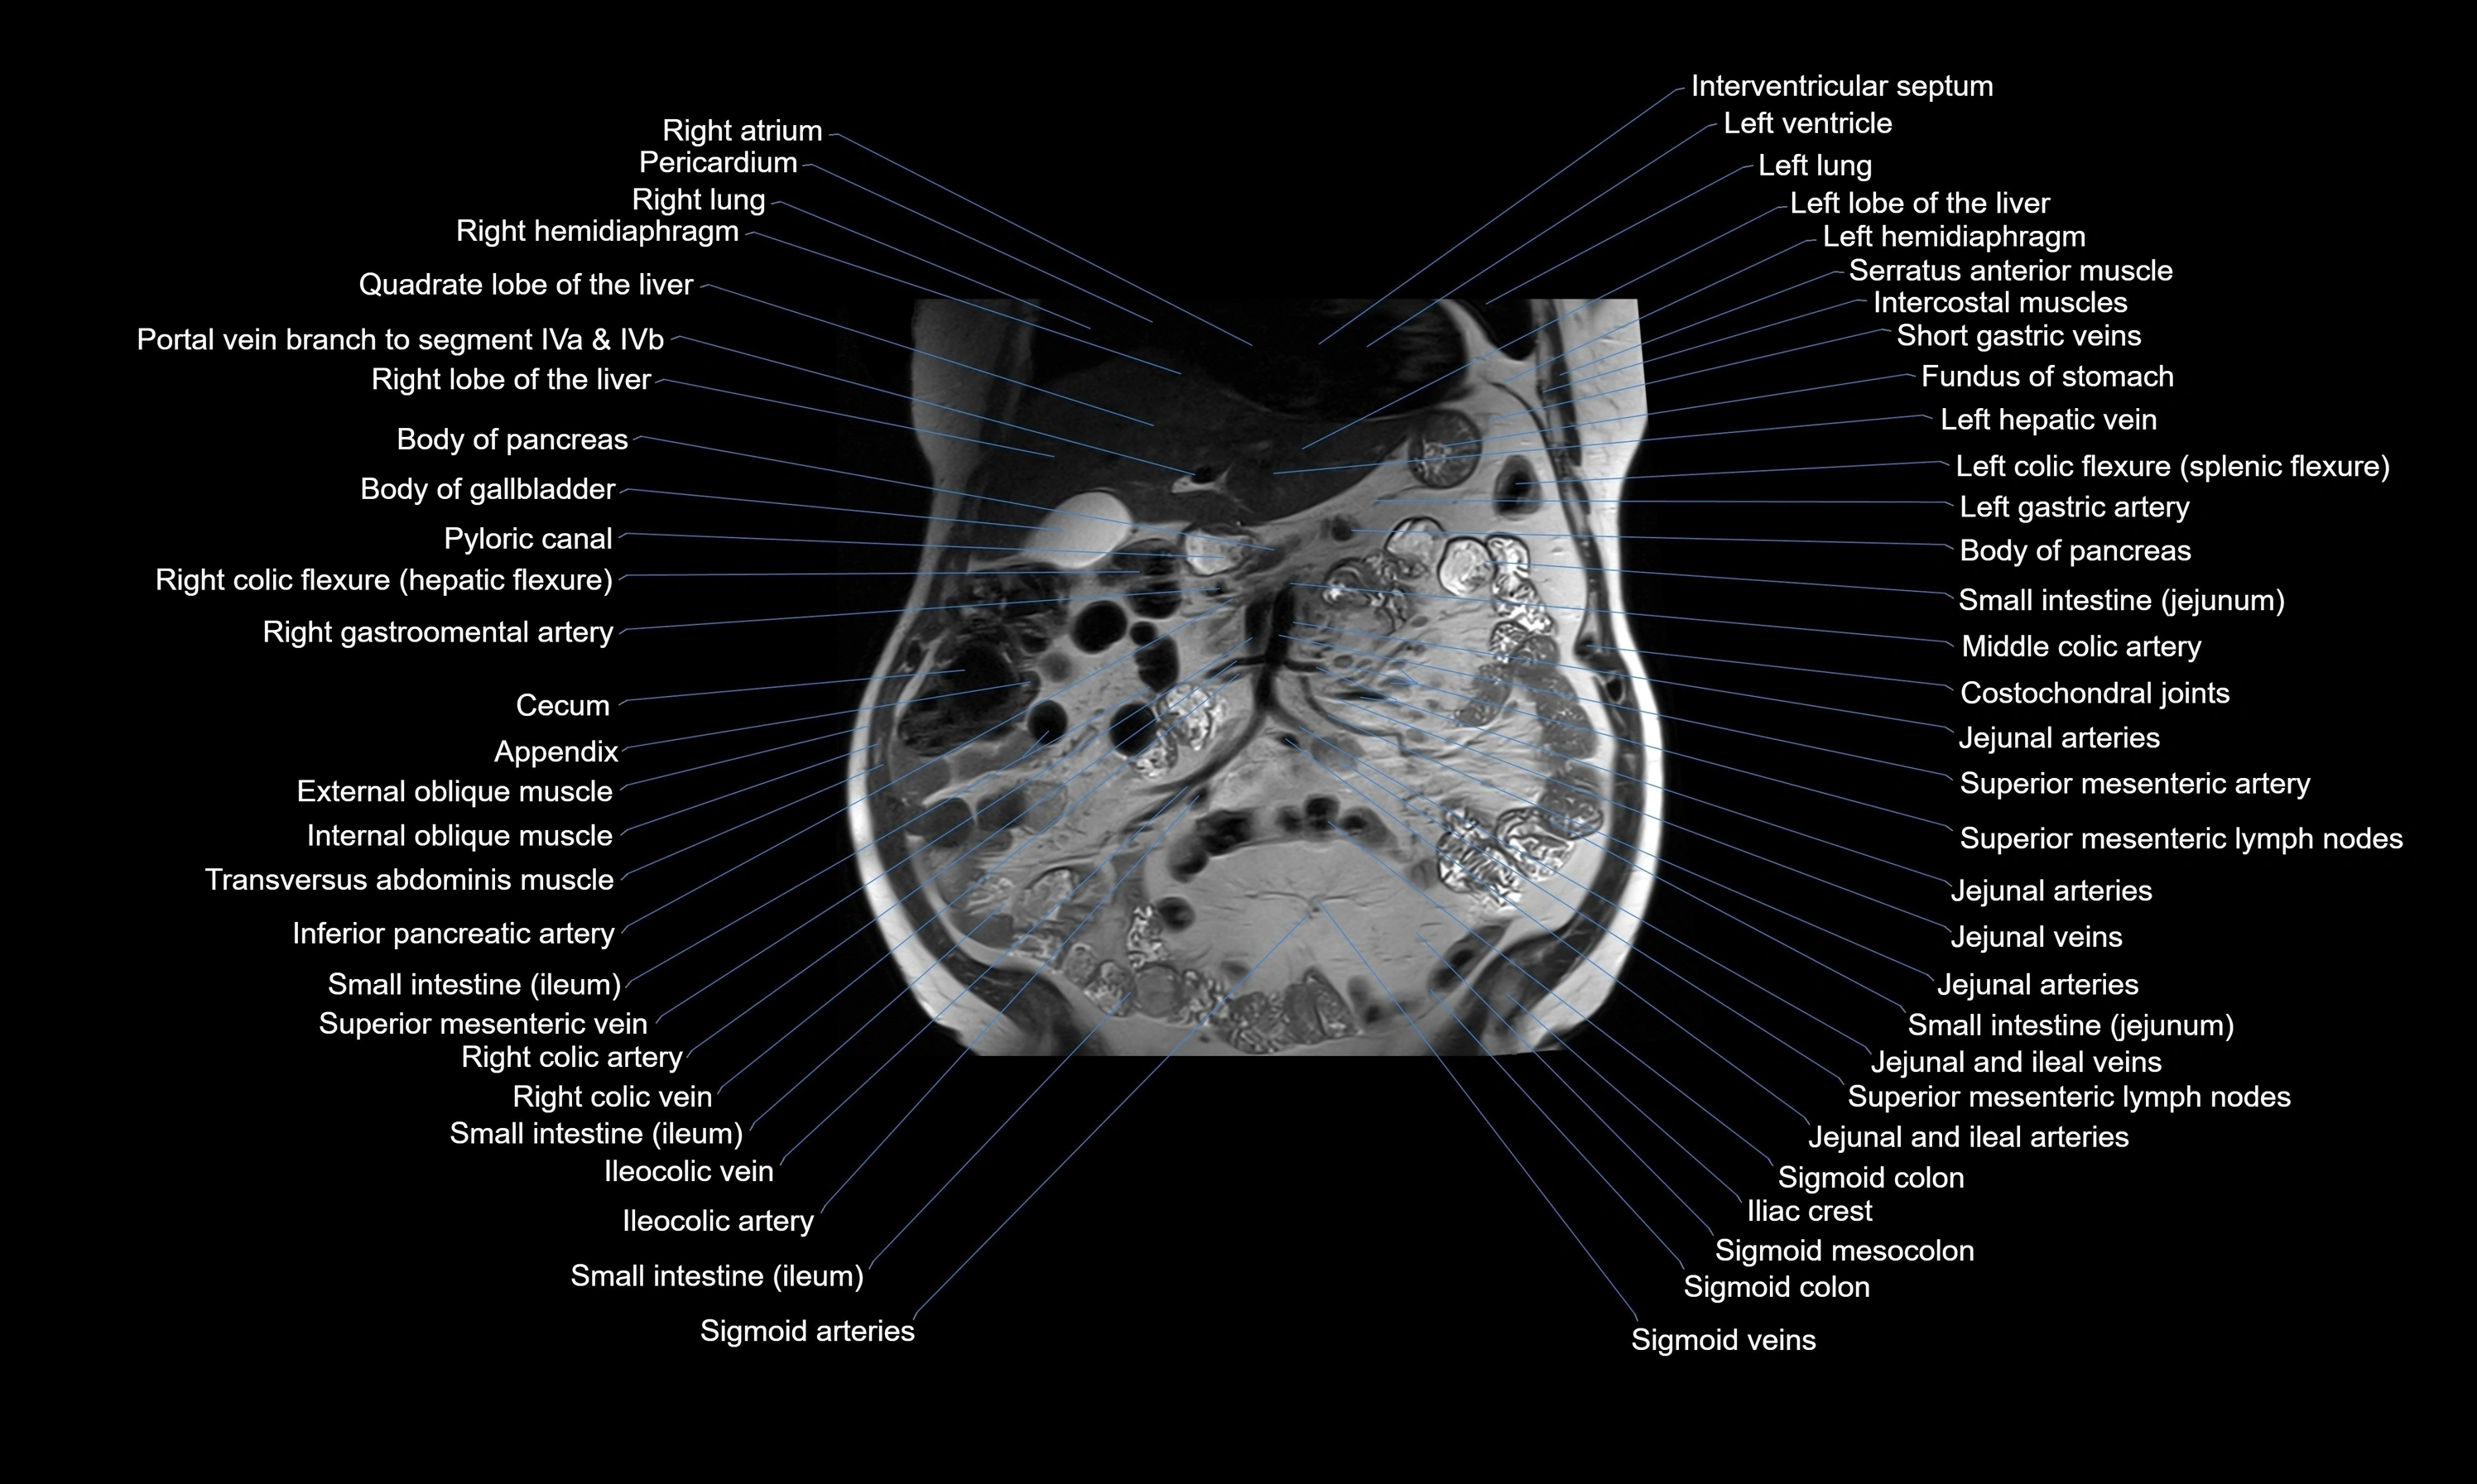

MRI images